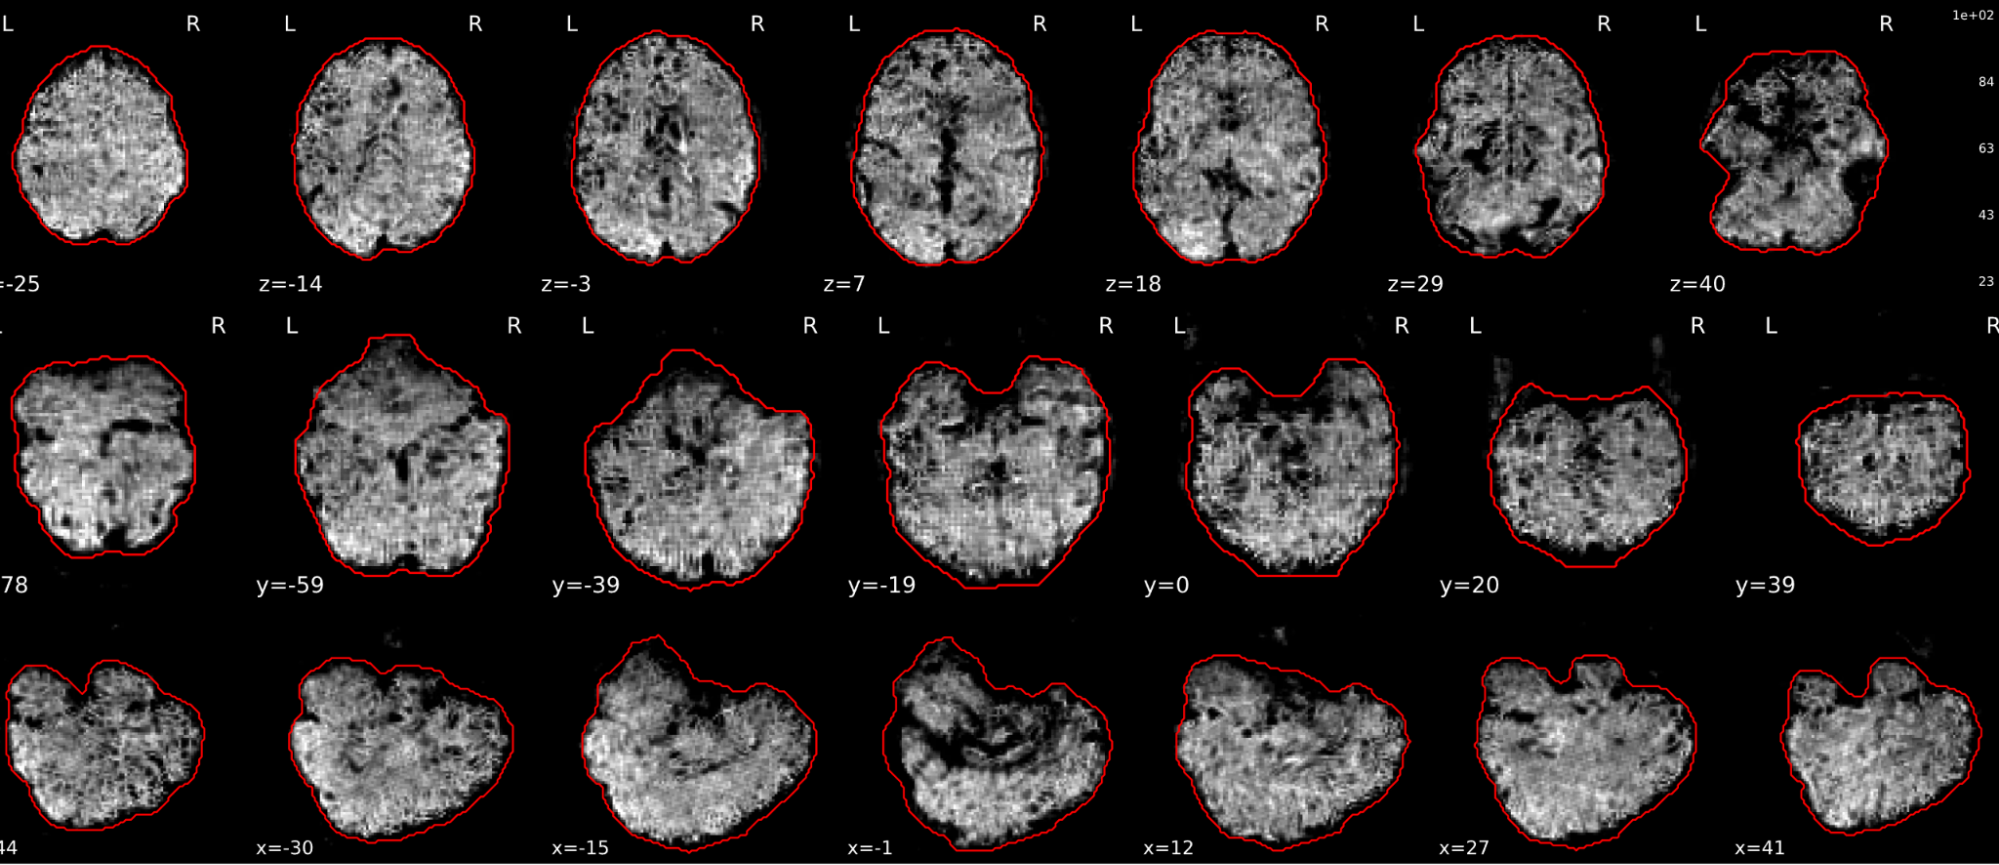

T1w skull stripping

Skull stripping is the process separating the brain (cortex and cerebellum) from the skull. The red line follows the outline of the brain and it separates it from the skull.

Example of a good subject

- There are no skull stripping errors, such as portions of the brain missing, or too much of the skull retained

- The red line follows the outline of the brain

Example of a bad subject

- There are skull stripping errors, such as portions of the brain missing, or too much of the skull retained

- NOTE: check all the images (slices) in the report. If only one image (slice) looks problematic, it is possible that the subject is okay and it is just a visual issue in that particular screenshot

Summary

| Good | Bad |

|---|---|

| The brain is fully inside the red line | Structures like the cranium or the eyes are inside the red line |

| No important brain structures are outside of the red line red line follows the natural outline of the brain | Important brain structures are missing inside of the red line |

-> if only one slice is problematic, it could be an issue related to the visual depiction of the data instead of an issue related to the test subject